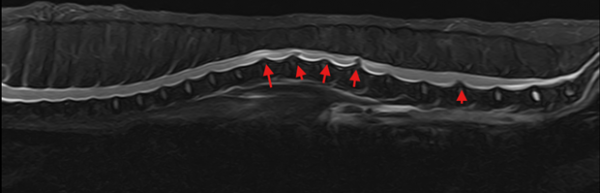

MRI 검사상, 본 환자에서는 흉추–요추 구간에 걸쳐

여러 개의 디스크 이상이 관찰되었습니다.

이렇게 여러병변이 동시에 발견된 경우에는,

현재 증상과 관련이 있는 부위를 감별하여

해당 부위에 대한 치료가 중점적으로 이루어져야

증상 개선을 기대할 수 있습니다.

신경 증상의 원인이 된 주요 디스크 병변

● 가장 중요한 병변

· L1–2 디스크 탈출 (severe extrusion)

→ 척수를 강하게 압박

→ 인접 척수의 타박(contusion) 및 수막염(meningitis) 소견 동반

└ 최근 발생한 뒷다리 마비 증상의 ‘주된 원인’으로 판단, 수술 고려

● 추가로 관찰된 병변들

· T12–13 디스크 탈출 (severe extrusion) 탈출된

디스크 조각이 본래 디스크와 분리된 sequestration 형태

└ 현재 증상과의 연관성은 있을 가능성은 있으나, 주원인은 아닌 것으로 판단

하지만 척수압박정도가 심하여 수술 고려

· T11–12 디스크 탈출 (chronic, severe)

오래된 병변으로 판단 척수 타박이나 염증은 동반되지 않음

척수공동증(syringomyelia) 관찰

└ 현재의 급성 증상과 연관성은 낮을것으로 판단됨

- 그 외 다발성 디스크 변화

T13–L1, L2–4, L4–5, L5–6, T7–10 등에서 protrusion 또는 bulging 관찰

일부는 인대 비후(yellow ligament thickening) 동반

└ 그러나 척수 압박 정도는 경미하여 내과적 치료 및 관리 시도